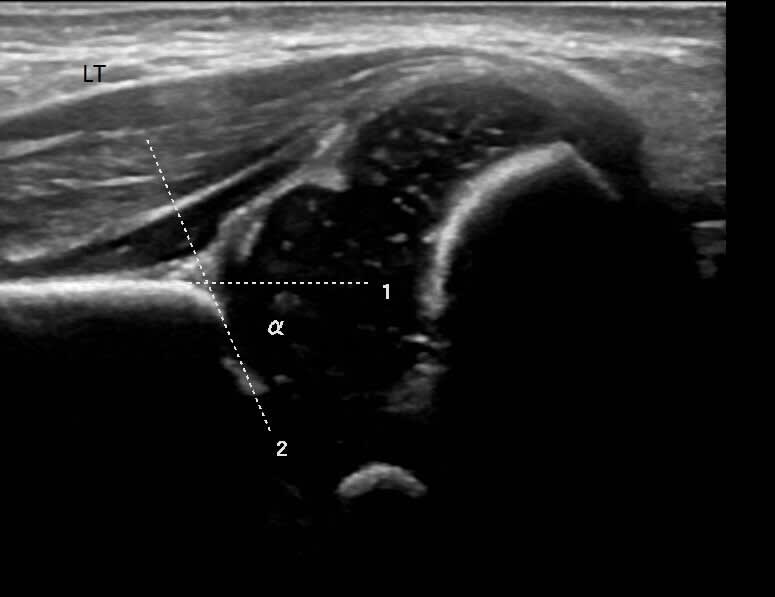

An ultrasound machine sends sound waves into the hip area, and images are recorded on a computer. The black-and-white images show the internal structures of the hip, including the ball-shaped top of the thighbone (femoral head) and its socket (acetabulum) in the pelvic bone.

Image courtesy of Dr Yusra Sheikh